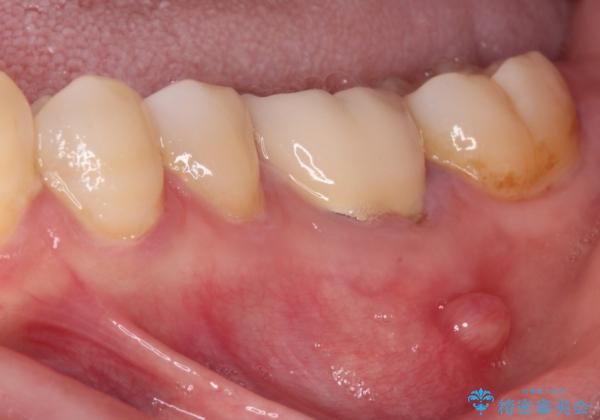

- 上下の奥歯に違和感を感じ、近医にて虫歯を指摘されたとのことで来院された患者様です。

診査したところ、下顎の奥歯は膿の出口ができており、上顎の奥歯は噛んだときに痛みを感じている状態でした。

まずは根管治療を行い、症状が落ち着いたことを確認して、オールセラミッククラウンにて補綴治療を行うこととしました。